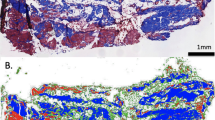

Commonly observed multifidus adaptations in individuals with LSP include increased accumulation of fat (Fig. 1), and collagen within muscle [10, 12, 13, 18,19,20,21]. Muscle atrophy has also been observed in some studies [13, 21,22,23,24,25,26,27]. Histological studies have similarly demonstrated muscle fiber degeneration [10, 19, 28], deposition of fibrotic tissues [10, 29, 30], increased inflammatory biomarkers [10, 31], and reductions in vascularity [10, 32] in paraspinal muscle biopsies from both humans and animals. Importantly, although paraspinal muscle degeneration has not been identified as a causal source for LSP, it has been associated with increased likelihood of symptom recurrence, poor post-operative outcomes, and reduced strength, endurance, and function, all of which may contribute to a poor prognosis in this patient population [7, 33,34,35]. The clinical implications of muscle health in the context of spine surgery is further highlighted by recent studies demonstrating a higher risk of proximal junctional kyphosis in patients with decreased back muscle volume and cross sectional area [36, 37]. Multifidus muscle degeneration was also associated with interbody cage subsidence in retrospective cohorts of patients undergoing both oblique and transforaminal lateral interbody fusions for LSP [38, 39].

Pathological muscle adaptations. T2-weighted axial MRIs of the lumbar paraspinal muscles (red outlines) from three different individuals, depicting muscle degeneration. Panel (a) depicts an individual with minimal fatty infiltration of the multifidus (M) muscle compartment. Panel (b) depicts an individual with moderate fatty infiltration, while panel (c) depicts an individual with high fatty infiltration. In conventional T2-weighted MRI imaging, muscle and fibrosis both appear dark and fatty tissue appears bright, as depicted above

Ten-micron sections of each tissue biopsy were obtained from OCT-embedded frozen samples using a Leica (CM3050S, Buffalo Grove, USA) cryostat. Hematoxylin and Eosin (H&E) and Gomori Trichrome stains were used to visualize gross muscle morphology and quantify tissue content [50]. ImageJ (http://imagej.nih.gov/ij) was used to automatically quantify the relative fractions of muscle, adipose, loose collagen, and dense collagen in Trichrome-stained biopsy [51]. Briefly, tissue type was determined by manual intensity thresholding of the red (muscle), green (loose collagen), and blue (dense collage) channels of whole-section RGB images, while adipose tissue was identified morphologically and traced [50, 52]. This methodology has been previously used and described in detail [10, 42].